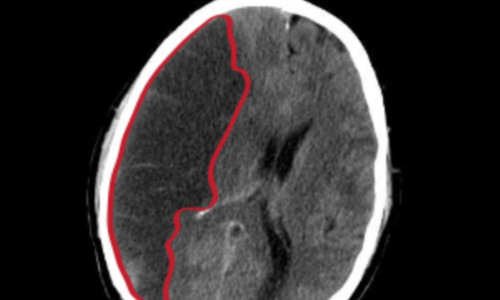

뇌졸중에서도 혈관이 막히는 뇌경색이야말로 촌각을 다투는 응급질환이라고 볼 수 있습니다. 뇌혈관이 막히면서 점차 뇌세포가 괴사하기 때문에, 증상 발현 3시간 안에 혈전용해제를 투여하고 시술에 들어가야 심각한 상황을 면할 수 있습니다. 뇌경색 치료방법에 있어 가장 중요한 것은 혈전을 녹이는 혈전용해제를 정맥 투여함으로써 막힌 혈관을 뚫어주는 것입니다. 하지만 혈전용해제의 경우도 출혈 가능성이 있는 환자에게는 투여할 수 없으며, 또한 혈소판 수치가 낮아서 지혈이 되지 않는 경우에는 제외된다고 합니다.

또한 과거에 이미 뇌출혈이 발생한 경우와 고혈압 환자의 경우도 혈전용해제를 투여할 수 없다으며 보통은 약50% 정도의 환자에게만 혈전 용해제를 이용한 치료가 가능합니다. 막힌 혈관을 뚫어주는 치료를 한 이후에도 뇌경색은 꾸준히 관리해야 하는데 재발할 확률이 높기 때문입니다. 따라서 약물치료와 함께 재활 치료가 필요하며 치료 이후 초기에 재활 치료를 적극적으로 해야 뇌경색 치료방법의 효과가 크고 후유증을 줄일 수 있습니다.